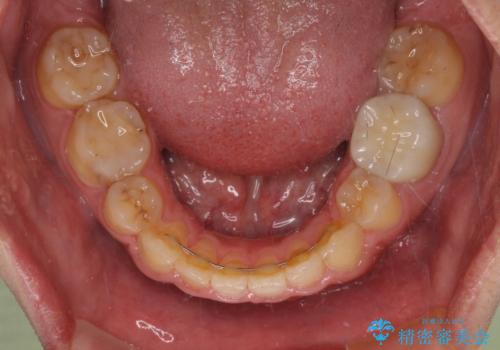

後戻りでデコボコの前歯 インビザライン矯正治療

下顎骨が左側に変位しているため、正中が合わないことは予想できましたが、歯列が整った後も咬み合わせが安定せず、咬み合わせを落ち着かせるために1年以上の期間を要しました。

噛みにくさの改善に時間がかかってしまうことがインビザラインの欠点の1つといえます。

- 矯正治療後の保定が不十分だと後戻り(元の位置に戻ろうとする動き)をします